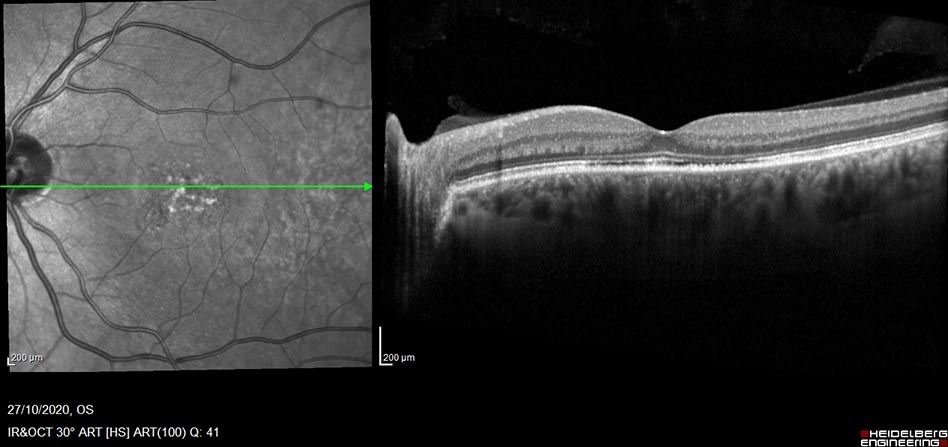

Finally OCT used in the education of patients about their diagnosis. In some instances it may be difficult for patients to comprehend and visualize what that are having treatment for. Healthcare professionals can use OCT to illustrate patients response to treatment and current state of the retina.

OCT Post treatment